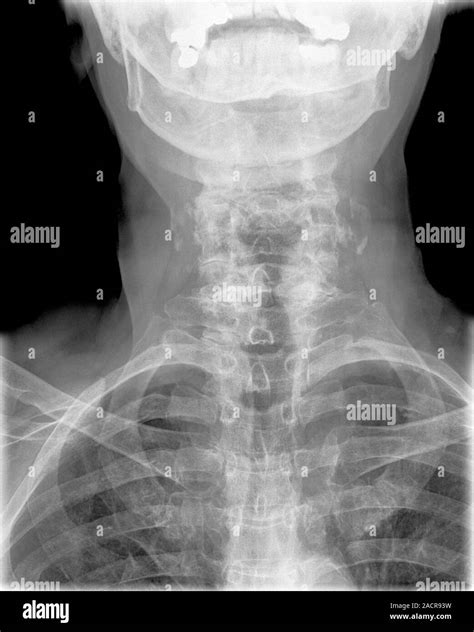

Diagnosing Arthritis in the Neck

Diagnosing arthritis in the neck typically involves a combination of medical history, physical examination, and diagnostic tests. Your healthcare provider may perform the following:

• Imaging Tests: X-rays, MRI, or CT scans to visualize the bones and soft tissues in the neck.

These diagnostic tools help determine the type and severity of arthritis, guiding the appropriate treatment plan.